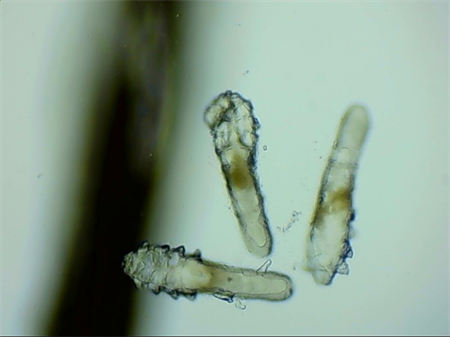

這就不得不提到眼科醫(yī)生經(jīng)常使用的螨蟲(chóng)檢測(cè)工具——螨蟲(chóng)鏡檢。它通過(guò)顯微利器,無(wú)死角全方位掃描你的睫毛,讓螨蟲(chóng)無(wú)處遁形。

▲螨蟲(chóng)鏡檢